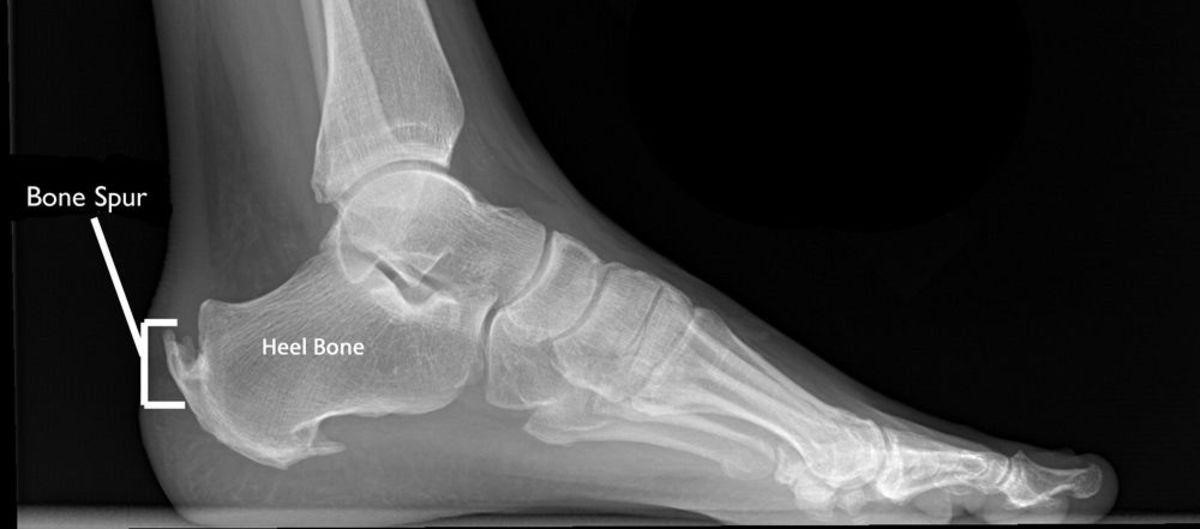

A bone spur (osteophyte) is an abnormal bony growth that forms when the body deposits extra calcium on the surface of bones. Bone spurs typically form in response to injuries such as osteoarthritis, joint trauma, and joint overuse. Bone spurs are usually smooth and benign but can cause wear and tear or pain if they press or rub on other bones or soft tissues such as ligaments, tendons, or nerves. Bone spurs commonly occur in the joints of the spine, shoulders, hands, hips, knees, and feet. Joint degeneration due to aging causes most bone spurs that form in the frequently used joints of the spine and feet. Besides joint injury including osteoarthritis, joint trauma, joint overuse and degeneration, a liver deficiency is another underlying cause of bone spurs.